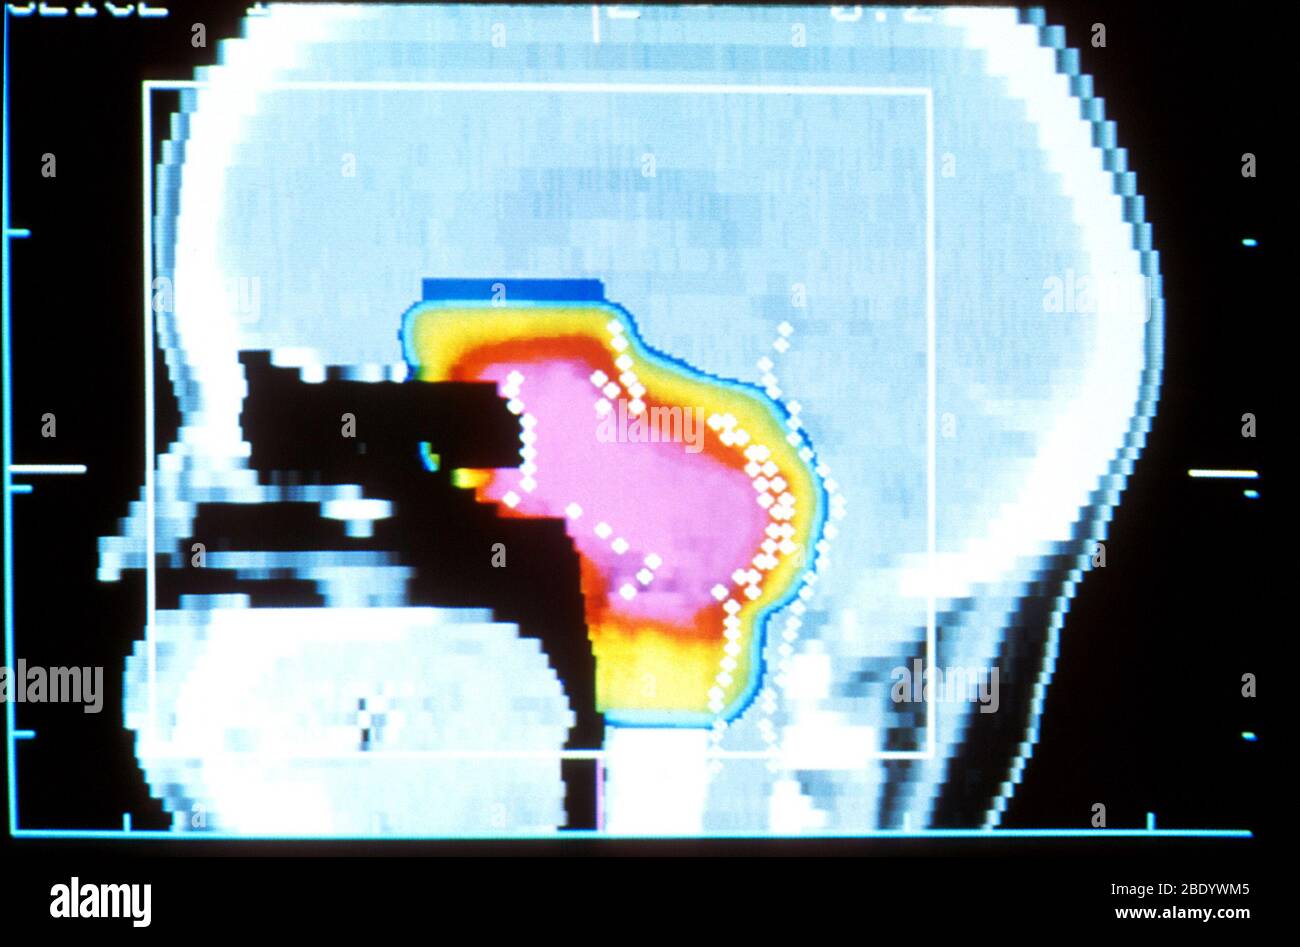

Protonthérapie Banque D'Imageshttps://www.alamyimages.fr/image-license-details/?v=1https://www.alamyimages.fr/protontherapie-image352810757.html

Protonthérapie Banque D'Imageshttps://www.alamyimages.fr/image-license-details/?v=1https://www.alamyimages.fr/protontherapie-image352810757.htmlRM2BDYWM5–Protonthérapie

Faisceau de protons du cerveau pendant l'acquisition CT Banque D'Imageshttps://www.alamyimages.fr/image-license-details/?v=1https://www.alamyimages.fr/faisceau-de-protons-du-cerveau-pendant-l-acquisition-ct-image352810717.html

Faisceau de protons du cerveau pendant l'acquisition CT Banque D'Imageshttps://www.alamyimages.fr/image-license-details/?v=1https://www.alamyimages.fr/faisceau-de-protons-du-cerveau-pendant-l-acquisition-ct-image352810717.htmlRM2BDYWJN–Faisceau de protons du cerveau pendant l'acquisition CT

Faisceau de protons du cerveau pendant l'acquisition CT Banque D'Imageshttps://www.alamyimages.fr/image-license-details/?v=1https://www.alamyimages.fr/faisceau-de-protons-du-cerveau-pendant-l-acquisition-ct-image352810720.html

Faisceau de protons du cerveau pendant l'acquisition CT Banque D'Imageshttps://www.alamyimages.fr/image-license-details/?v=1https://www.alamyimages.fr/faisceau-de-protons-du-cerveau-pendant-l-acquisition-ct-image352810720.htmlRM2BDYWJT–Faisceau de protons du cerveau pendant l'acquisition CT